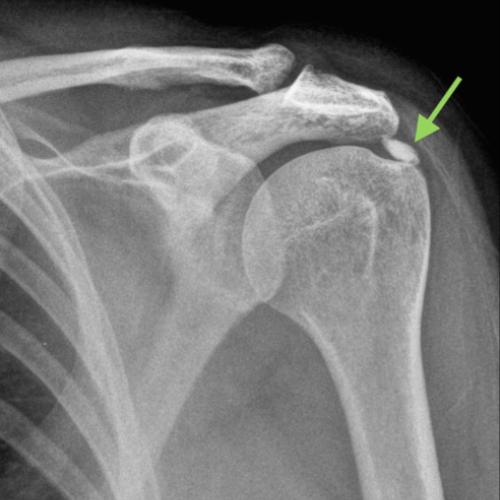

Shoulder pain can stem from many causes—rotator cuff injuries, frozen shoulder, tendonitis, bursitis, arthritis, or nerve impingement. While symptoms often feel similar, effective relief depends on accurately identifying the underlying condition. At REGENIQUE, we use advanced diagnostic tools and image-guided assessments to get to the root of your pain, ensuring that treatment is precise and recovery is long-lasting.

Calcific Tendinitis

Dr. Tushar B Munnoli is trained in ultrasound-guided pain interventions that offer faster diagnosis and targeted relief for shoulder disorders.

We use clinical evaluation and musculoskeletal ultrasound to identify the source of pain and tailor a targeted treatment.